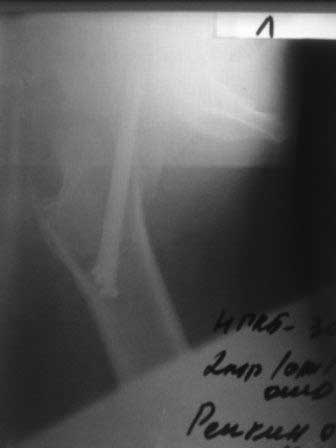

Обратился б-ной около 40 лет, три месяца назад оперирован в г.Алмате. При осмотре ходит с двумя костылями, беспокоят постоянные боли, симптом прилипшей пятки положительный, посмотрел под Р-скопией; сращения нет.

Понимаю, показано эндопротезирование, но  можно  ли органосохраняюшие операции с  аутопластикой? Остеосинтез выполнен не совсем правильно (три винта должны быть расположены субкортикально, а не в ряд, поэтому имеется плохая ротационная стабильность). Но стояние фрагментов правильное, 3 месяца для шейки не срок. Отложите вопрос о протезировании еще на 3 месяца, есть шанс срастить перелом при исключении нагрузки.  При выполнении органосохраняющих операций результат будет хуже, чем при протезировании.

P.S.   Р-снимки сразу после операции,  и вчерашные.